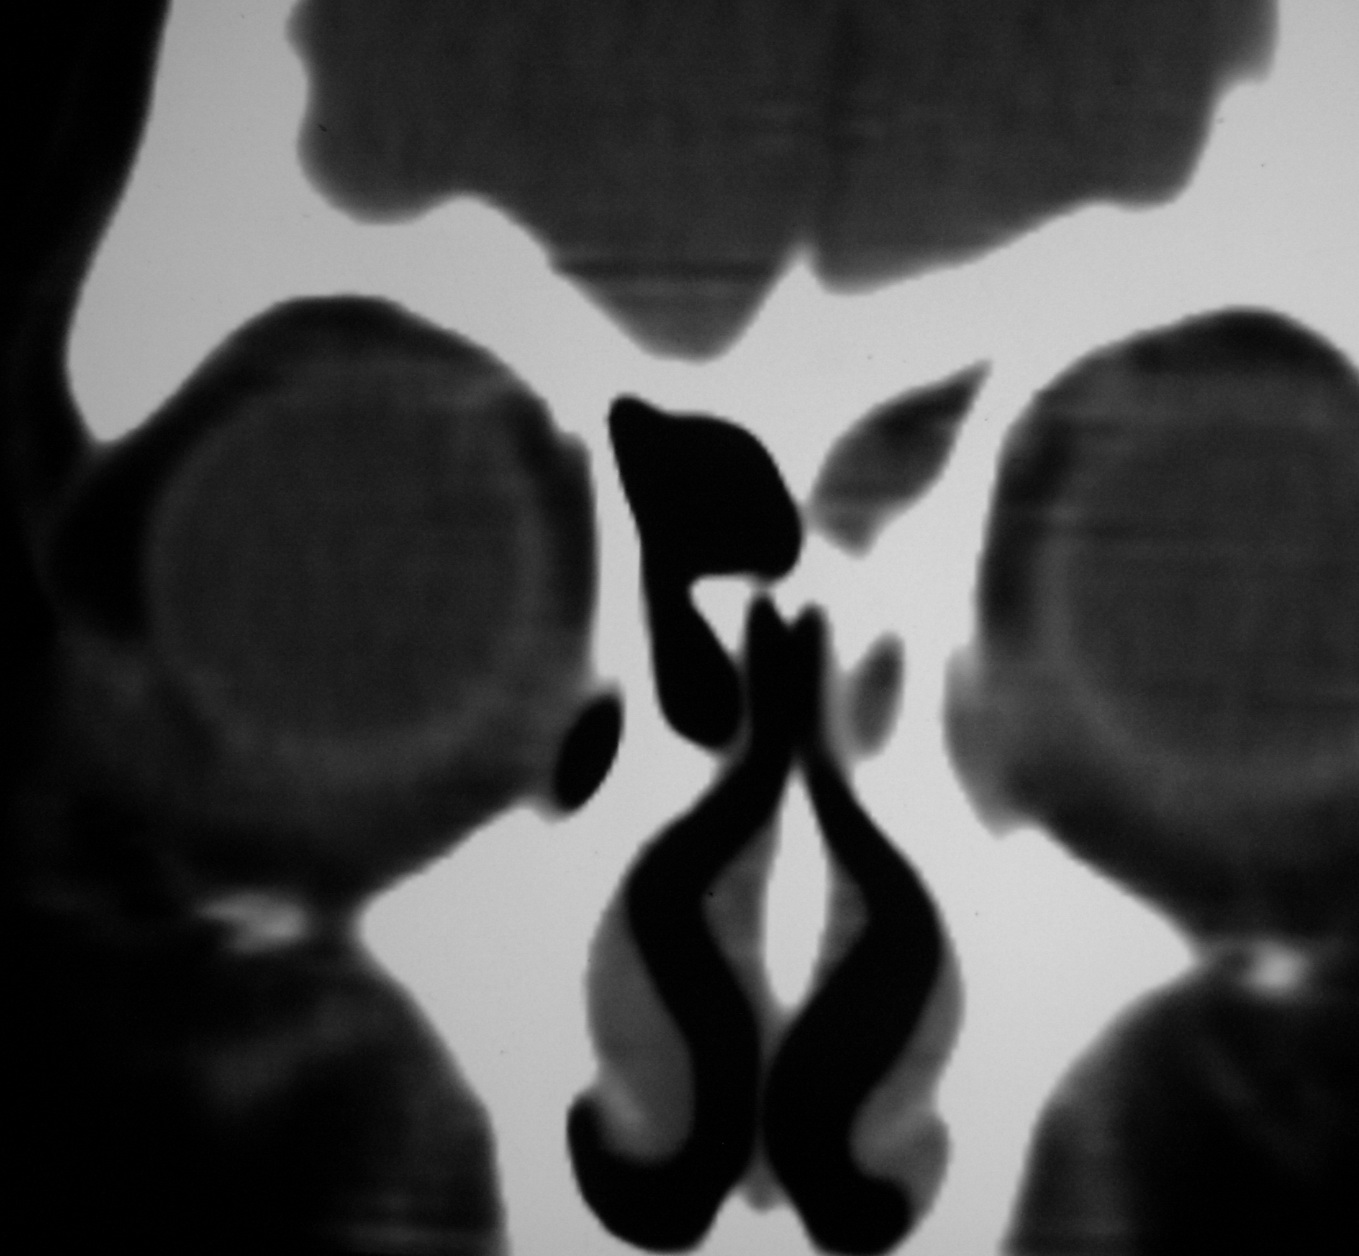

右侧眼眶脂肪瘤

女,34岁。右眼不适半年。

会员诊断:

表皮样囊肿、皮样囊肿、脂肪瘤

手术病理

:右侧眼眶

脂肪瘤

。